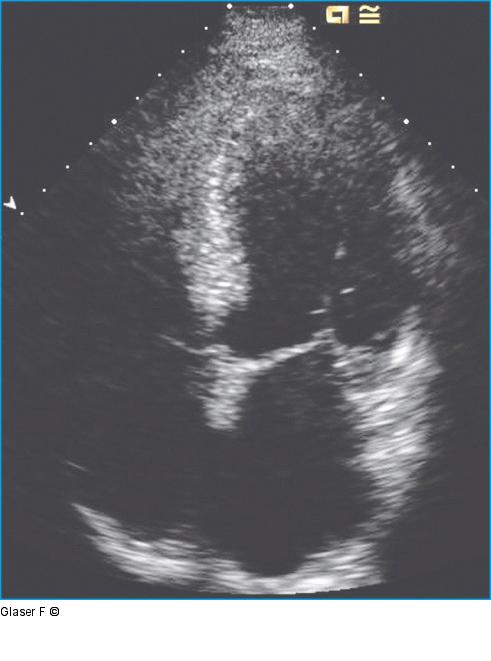

Abbildung 1: Vierkammerblick Apikaler Vierkammerblick: Global mäßig reduzierte Linksventrikelfunktion, vergrößerter linker Vorhof, laterale Hypo- bis Akinesie. |

Apikaler Vierkammerblick: Global mäßig reduzierte Linksventrikelfunktion, vergrößerter linker Vorhof, laterale Hypo- bis Akinesie. |